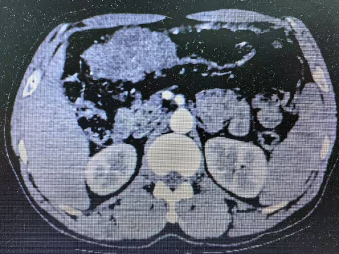

老年患者郑某某,男,60多岁,以“上腹部胀满不适1月余” 之主诉于2023年12月入住老年普外科大明宫院区(普外科四病区)王志东教授团队组。入院行胃镜检查显示胃窦癌,胃潴留,慢性萎缩性胃炎,反流性食管炎。病理活检示胃窦粘膜中-低分化腺癌(图三所示)。上腹部增强CT回报示胃窦、横结肠及其间隙内近9cm肿块型肿瘤,结肠侵犯可能,如图一所示。术前临床分期:cT4bN2M0(IIIb期)也就是通常称呼的局部晚期胃癌。将术前检查评估情况告知家属后,听到局部晚期胃癌的噩耗,家属近乎绝望。王志东教授团队耐心的和病人及家属沟通后,联合肿瘤科、影像科、老年医学科等进行了肿瘤多学科诊疗和老年病多学科诊疗(MDT)后,对该患者实施了6个周期的化疗和PD-1免疫治疗,期间患者适应性良好,未出现严重不良反应。

2023年12月CT结果 腹腔可见巨块型肿瘤